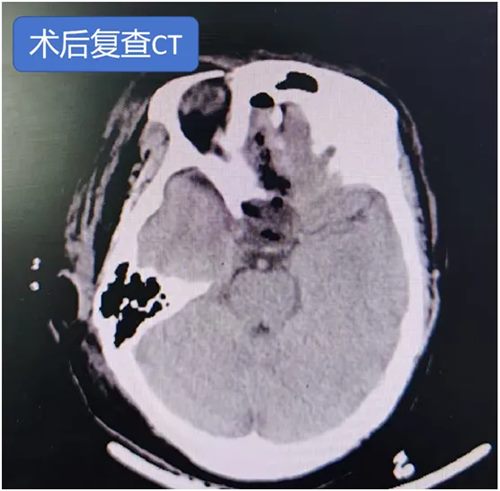

马建主任和周少龙副主任术前详细阅片并在脑海中反复预演手术过程,制定了周密的手术方案,经过2小时精细操作,成功实现肿瘤全切,所有关键神经血管结构毫发无损。术后患者左侧视力得以保留,头痛症状消失,无尿崩、眼球运动障碍等并发症,在鲁小丽护士长带领的护理团队的精心护理下恢复良好,目前已顺利康复出院。

手术在神经电生理科孙楹老师的实时监测下进行,术中肿瘤与周边神经血管,尤其是岩静脉粘连紧密,仅历时1个半小时,即实现全切肿瘤,术后患者耳鸣消失,听力正常,无面瘫、面部麻木等不良反应。